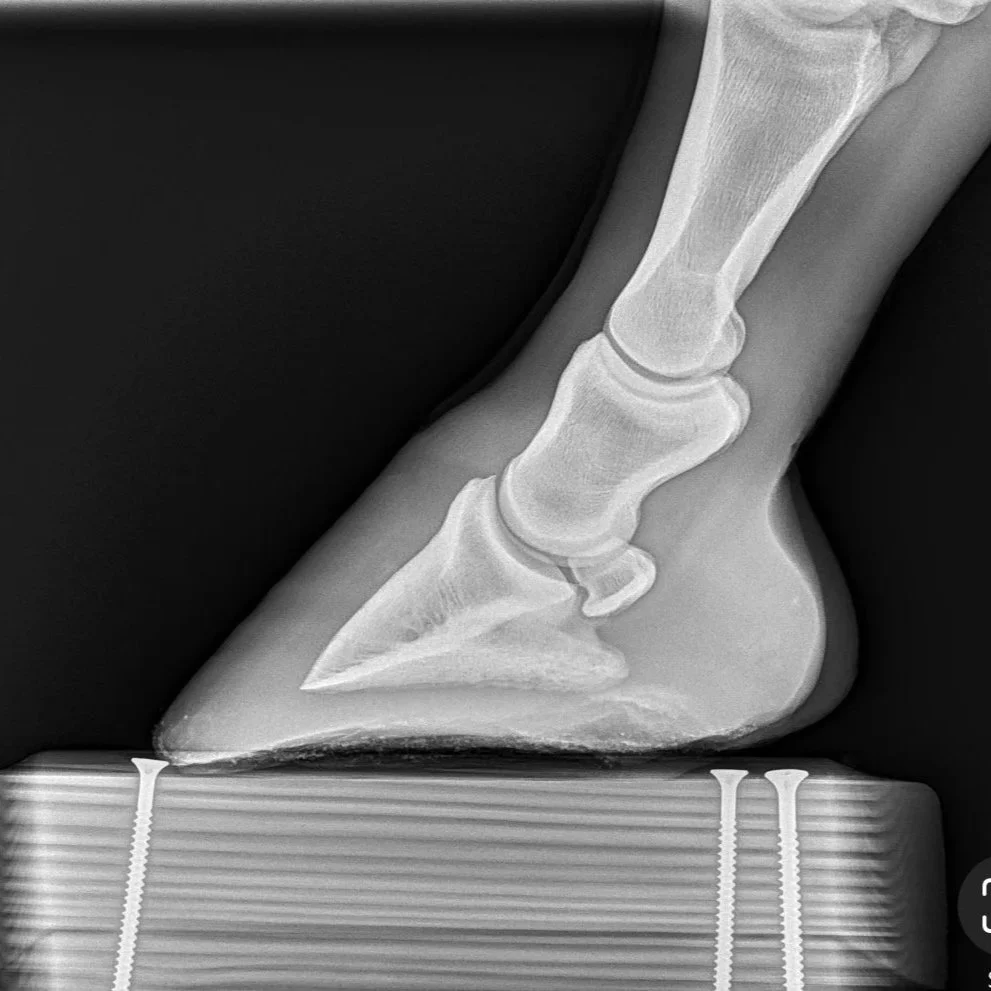

Right hind: Coffin bone is 2* NPA

Radiograph belonging to this RH

This is a radiograph of her right hind, which is NPA